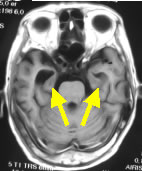

74歳女性 アルツハイマー病 海馬(矢印)が萎縮し脳室拡大(+)